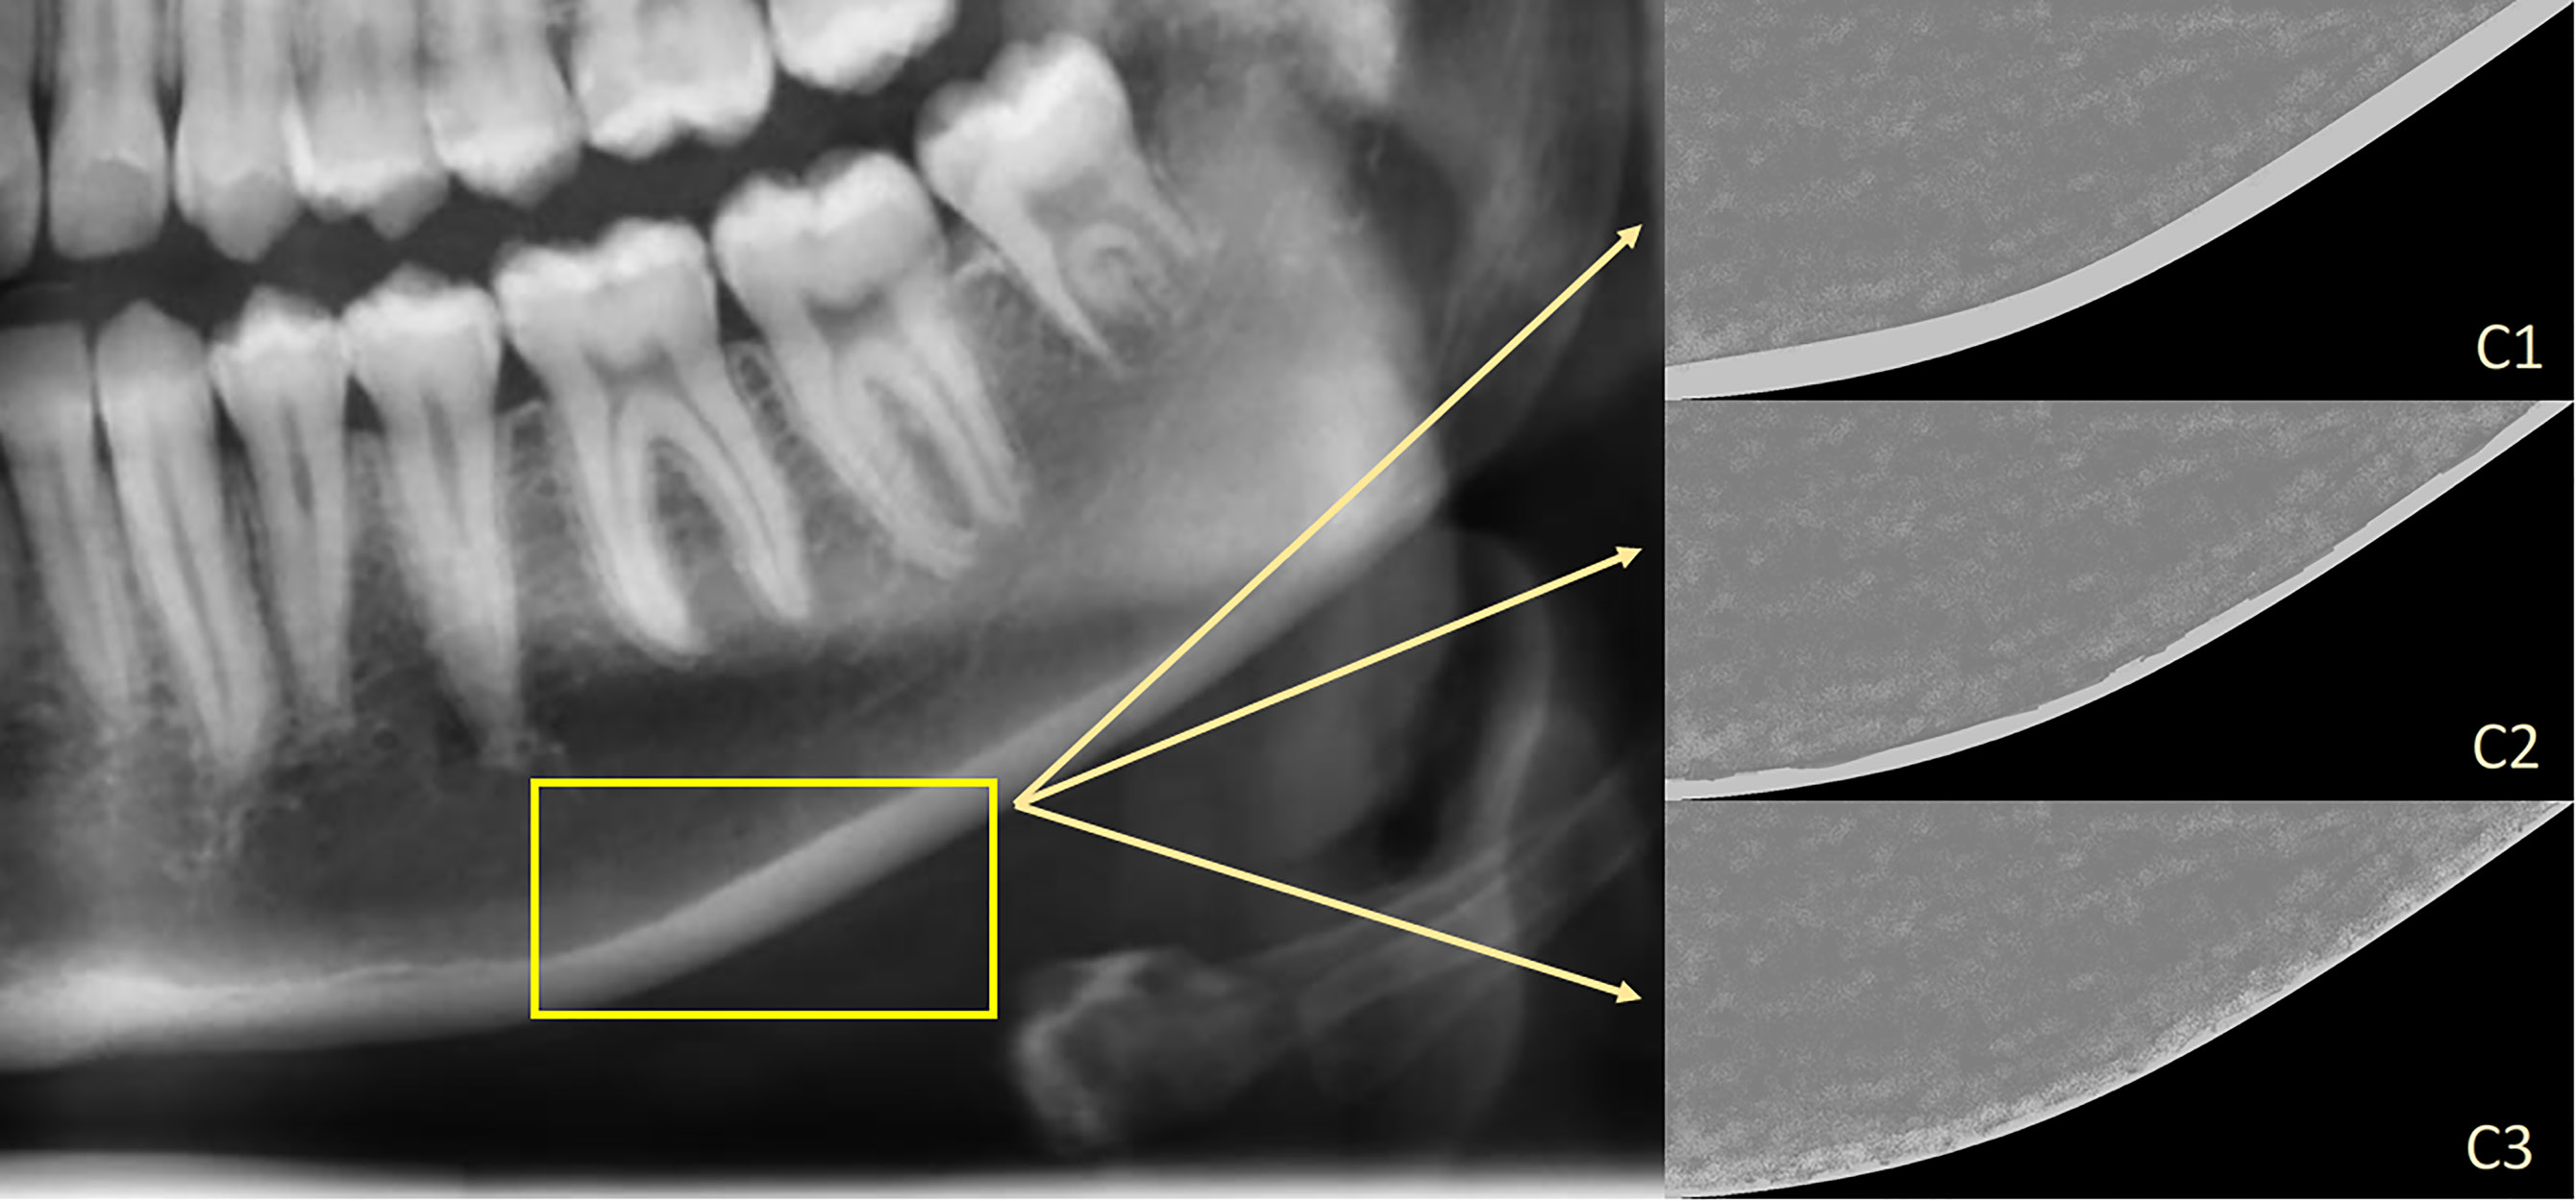

The appearance of the mandibular cortical bone, distal to the mental foramen, was evaluated bilaterally to make a classification. The classification was made according to KI and described as22:

– C1 – the endosteal margin of the cortex is homogenous, even and sharp (bilaterally);

– C2 – the endosteal margin of the cortex displays semi-lunar defects (lacunar resorption) or endosteal cortical residues (unilaterally or bilaterally); and

– C3 – the cortical layer is porous and displays endosteal cortical residues (Figure 4).